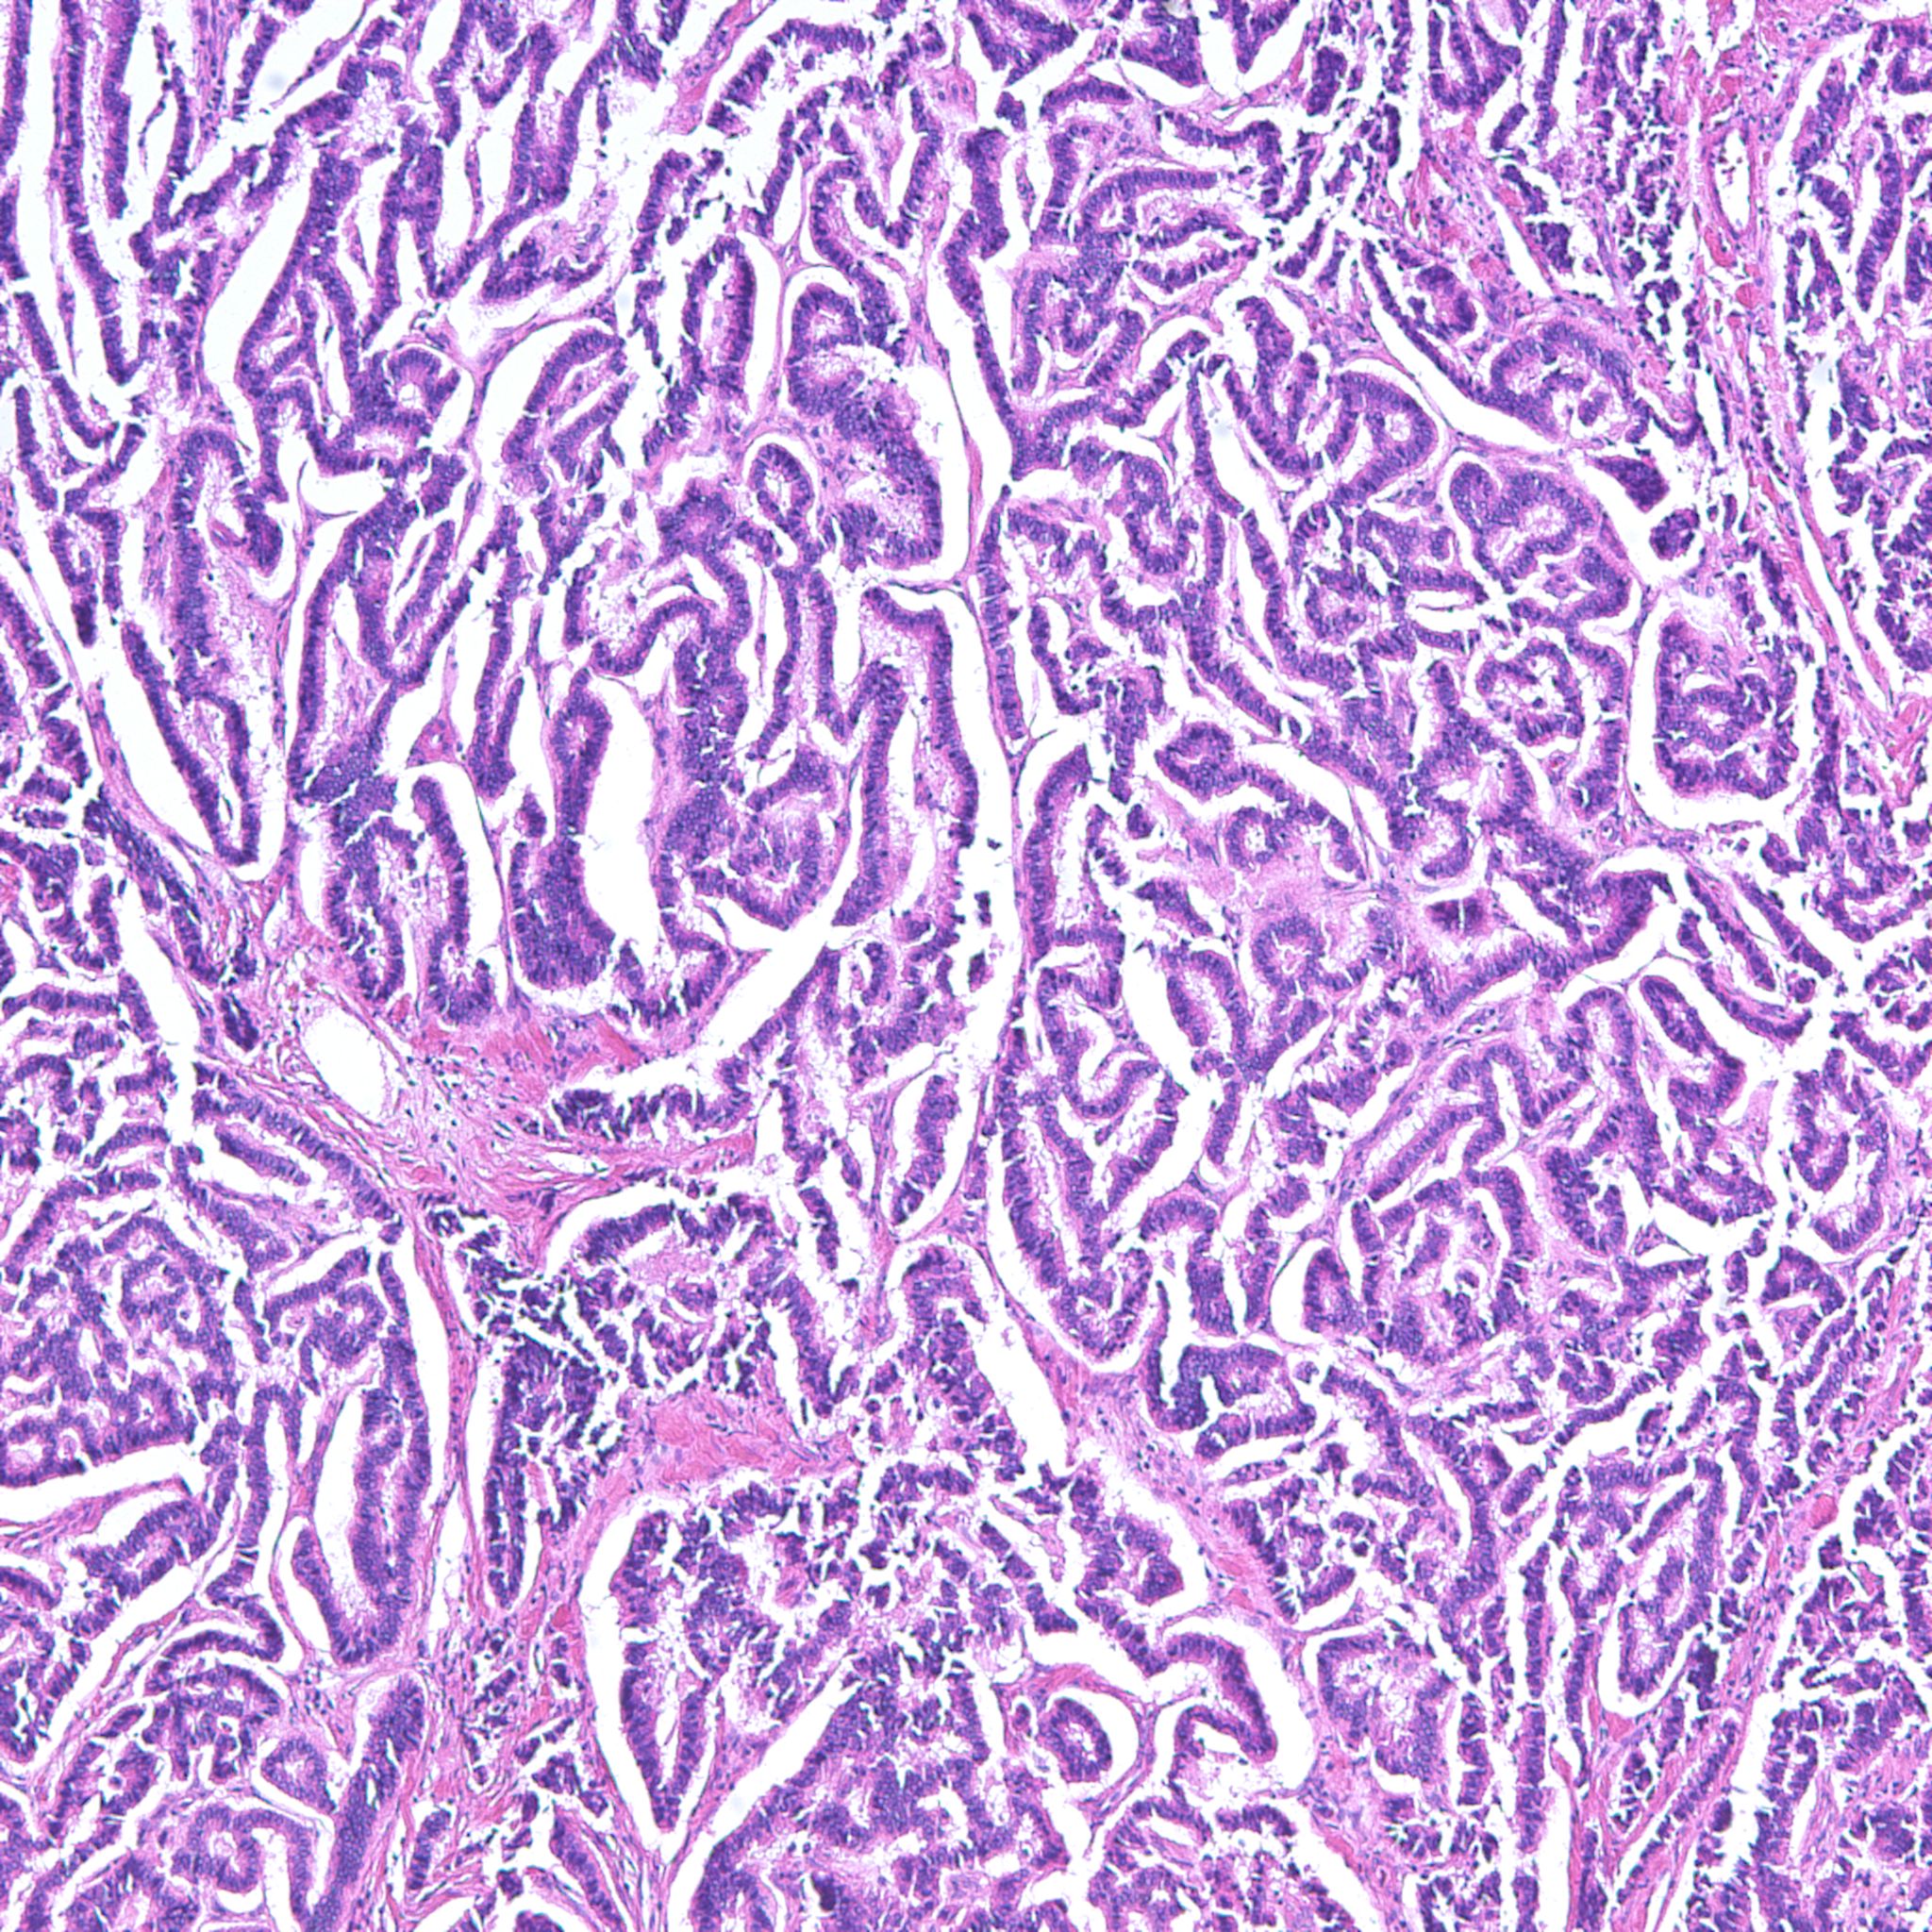

Classification of renal tumors

Case ID: 1230